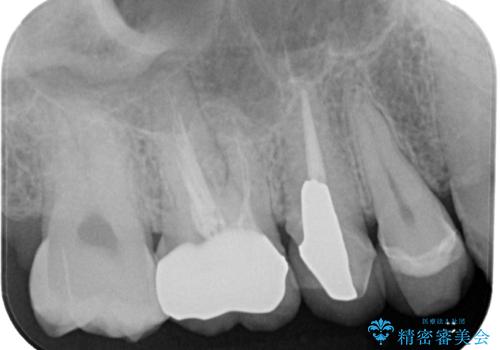

- セラミックが欠けたとのことで来院された患者様です。新しくセラミックを作り直していく治療計画としました。

拡大鏡視野下で、セラミックの被せもの、虫歯の除去を行い、オールセラミッククラウンに適した形に整えました。

咬み合わせが強く以前のセラミックを割ってしまっているので就寝時にはナイトガードを使ってもらう予定です。

今後もメンテナンスで通っていただきながら、経過観察していく予定です。